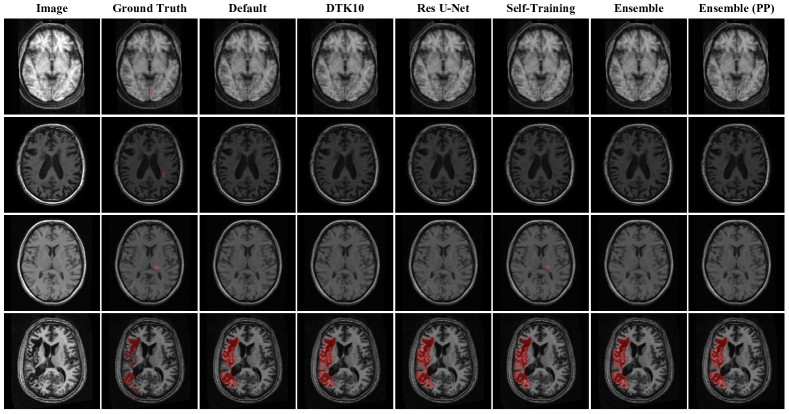

The ATLAS v2.0 [10] is a new dataset built upon ATLAS v1.2 to address the aforementioned concerns. ATLAS v2.0 contains 1271 T1-weighted MRIs with manually annotated lesion masks collected from 44 different research cohorts across 11 countries worldwide. Furthermore, it splits all subjects into three sets: the training set, the public test set, and the hidden test set. Participants can use the training set for model design and parameter tuning, and submit the label predictions of the public test set and docker image for the hidden test set via the online evaluation platform111https://atlas.grand-challenge.org/ to evaluate their models. Here, we show some exemplar images contained in the training set in Fig. 1, and we can see the large variance of stroke lesion shapes and sizes in the set. Additionally, ATLAS v2.0 is the dataset for MICCAI 2022 Stroke Segmentation Challenge 1. 18 teams participated in this challenge and 7 teams submitted their final solutions.

Refer to caption

Figure 1: (a) Exemplar images of small lesions. (b) Exemplar images of big lesions. Exemplar images indicate the large variance of stroke lesion shapes and sizes in ATLAS v2.0 dataset.